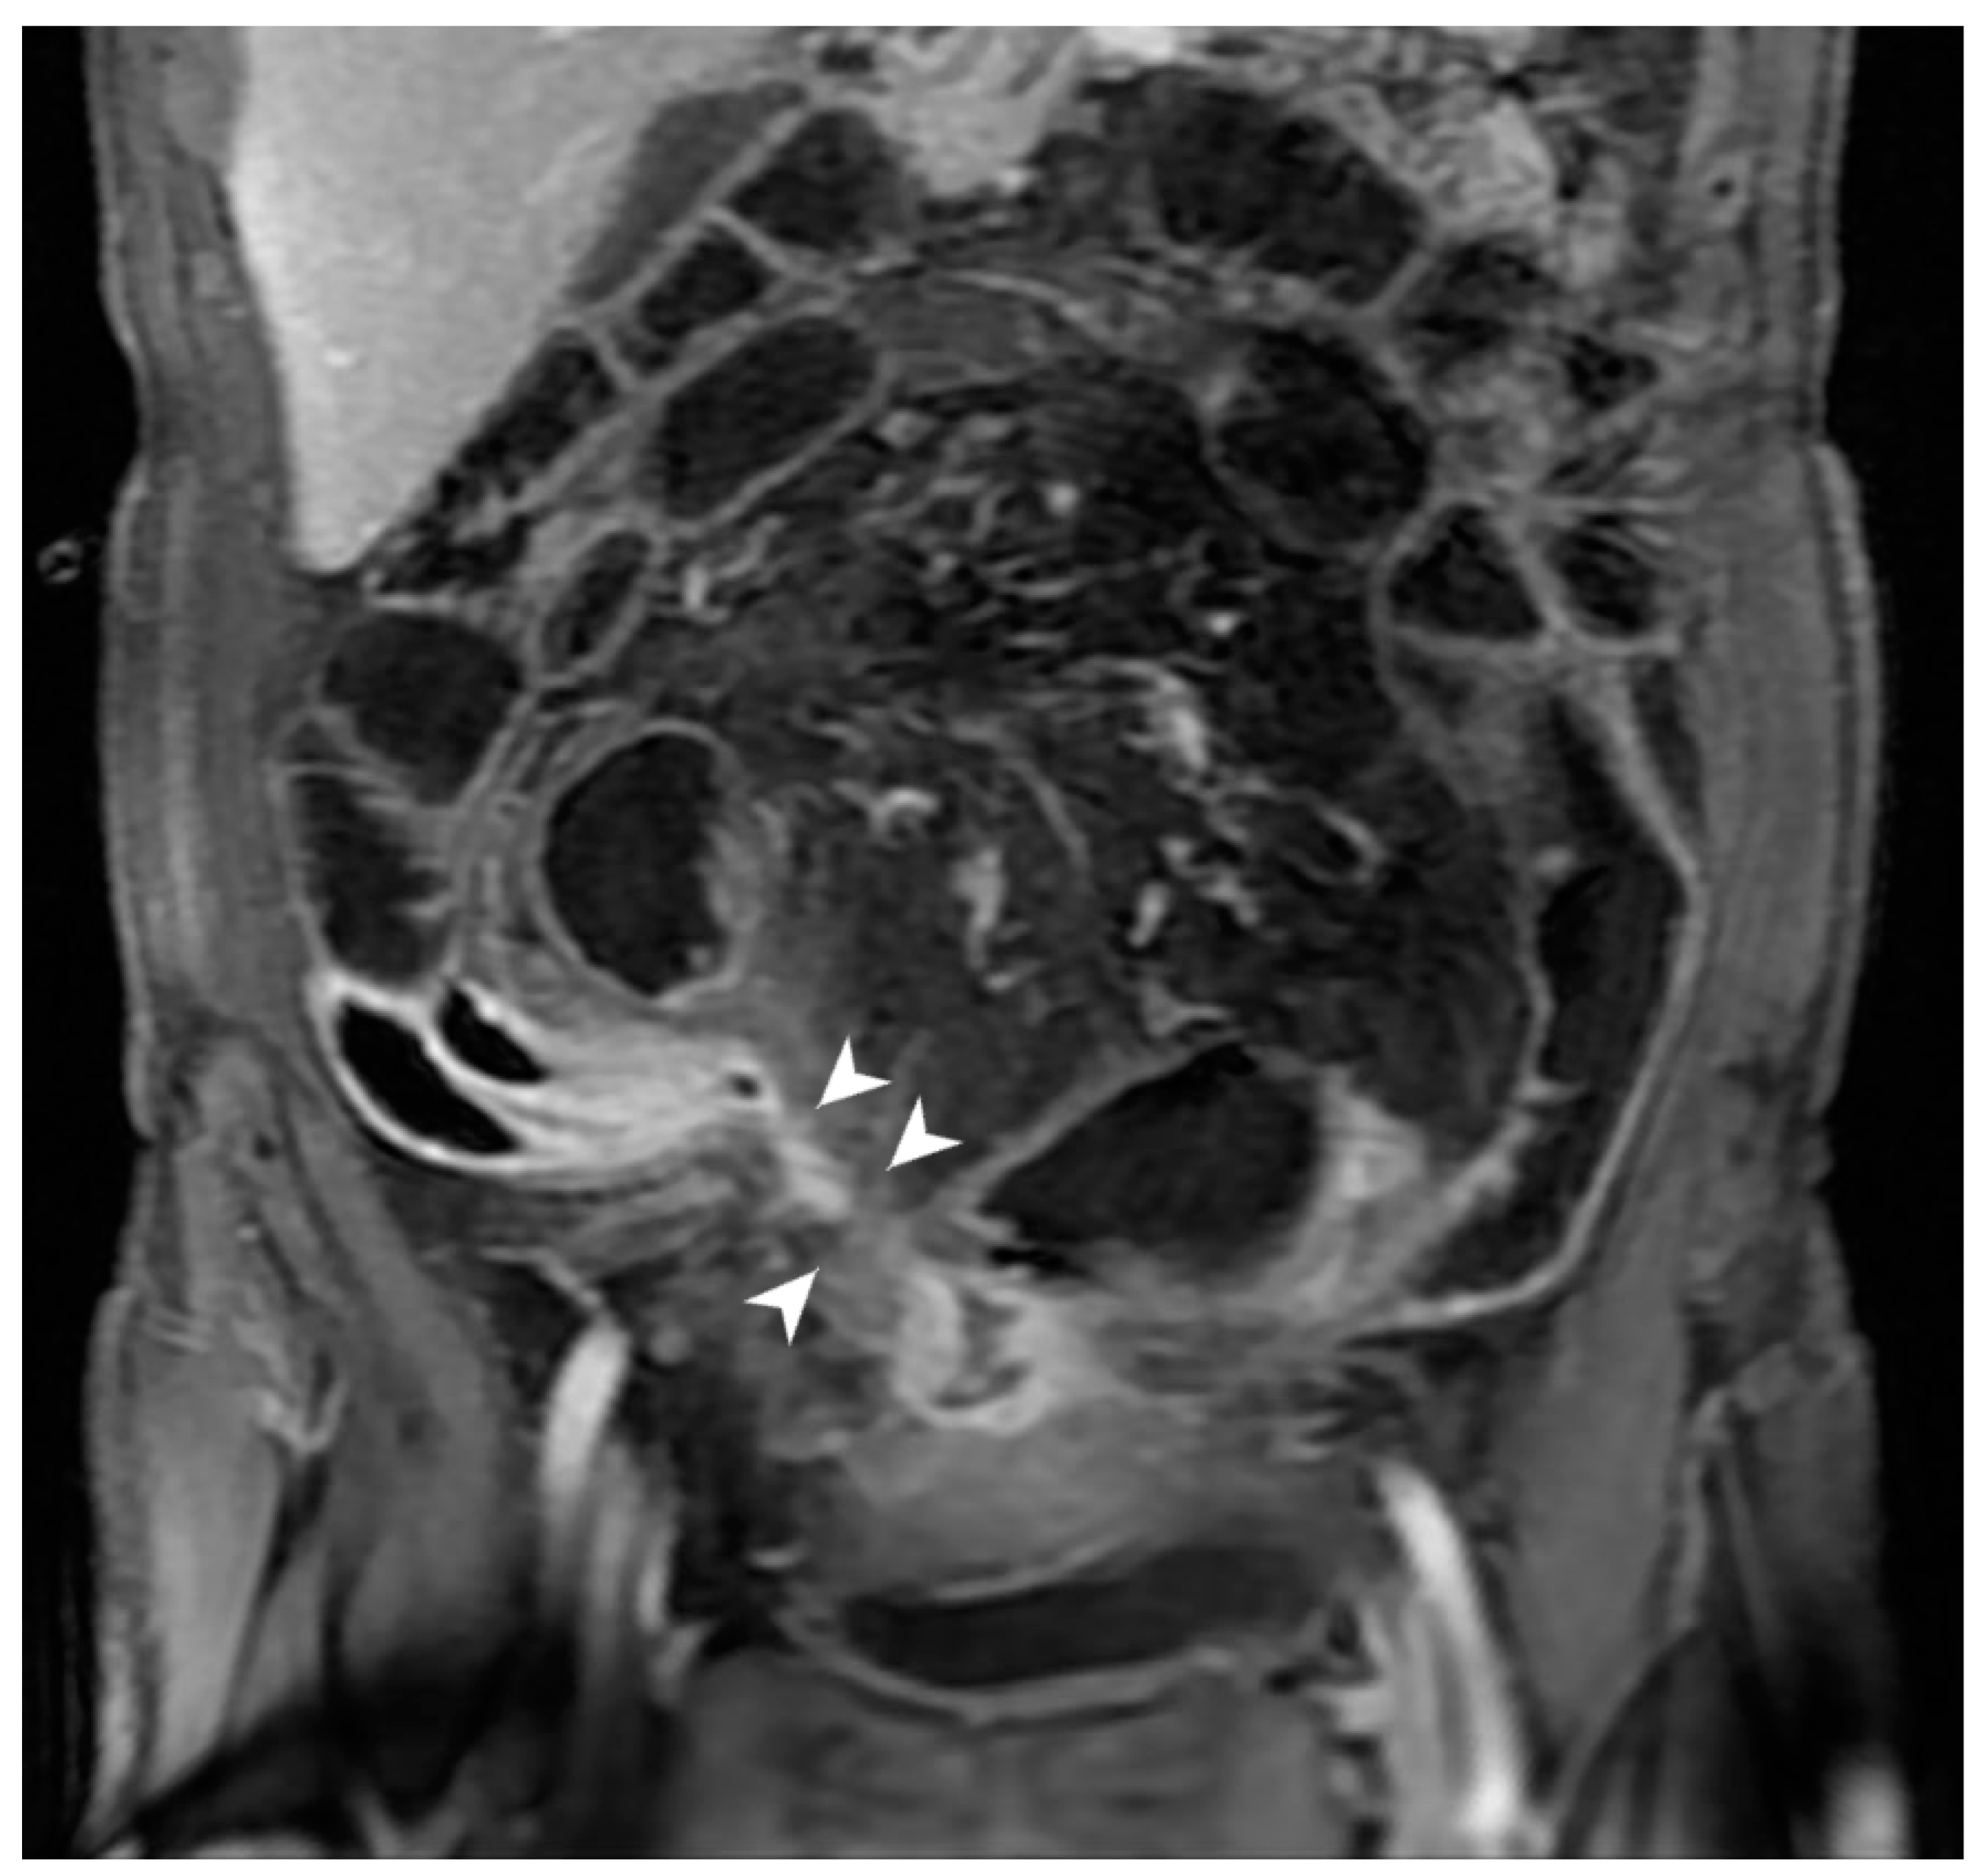

5.3. Fistulising/Perforating Subtype